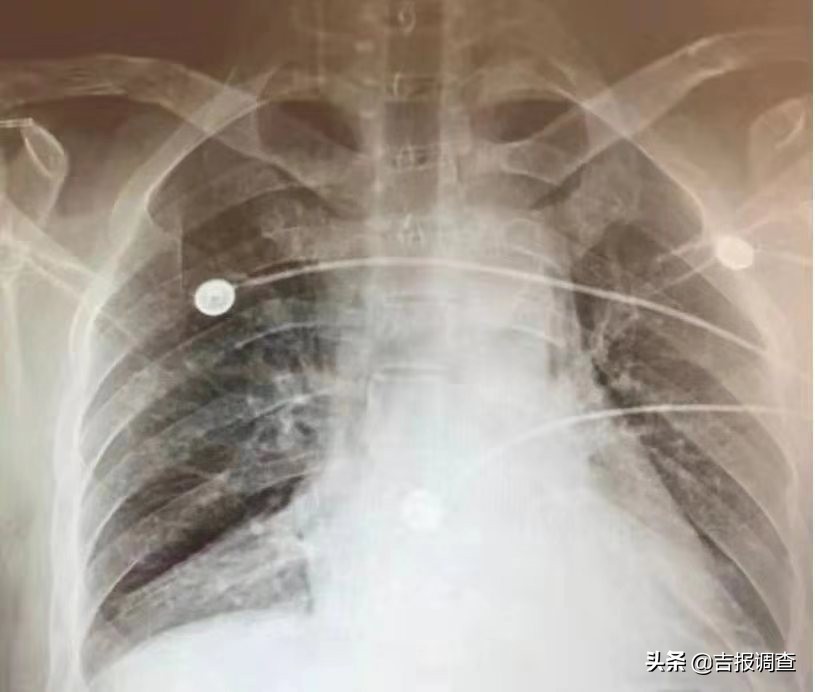

高仁助在术后恢复良好,术后第一天就能下床自如活动,双肺复张情况也达到了预期结果。

术后第一天床旁胸片